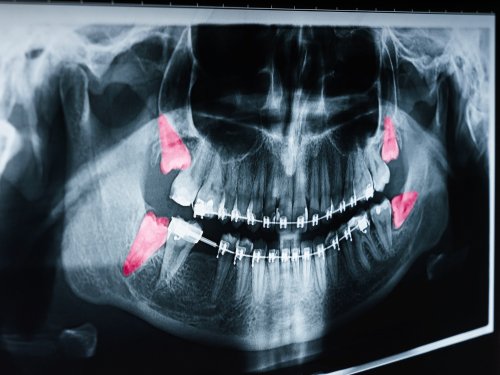

Wisdom Teeth: When to Extract and What to Expect

Understanding Your Third Molars Hello, I’m Dr. Justin Raanan. If you have been feeling a dull ache in the back of your jaw or noticing some crowding in your smile,